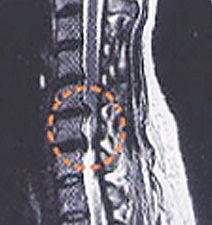

MRI는 뼈와 신경, 디스크를 완전히 구분하여 보여주어 목 디스크의 진단을 더욱 세밀하고 쉽게 할 수 있습니다.

진단은 앞에서 말한 증상으로도 어느 정도 가능하며 방사선학적 검사로 확진이 가능합니다. 방사선검사 X-ray 및 CT검사로 더욱 정확하고 쉽게 목 디스크의 진단을 할 수 있습니다.

CT는 종, 횡으로 잘라서 볼 수 있고 신경과 디스크가 서로 다르게 나타나기 때문에 디스크에 의해서 신경이 누른 모습을 직접 볼 수가 있고 조영제를 주입하여 더욱 선명하게 볼 수 있습니다.